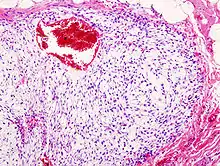

| Histopathologic image of chondrosarcoma of the chest wall. Surgical resection of recurrent mass. H & E stain. | |